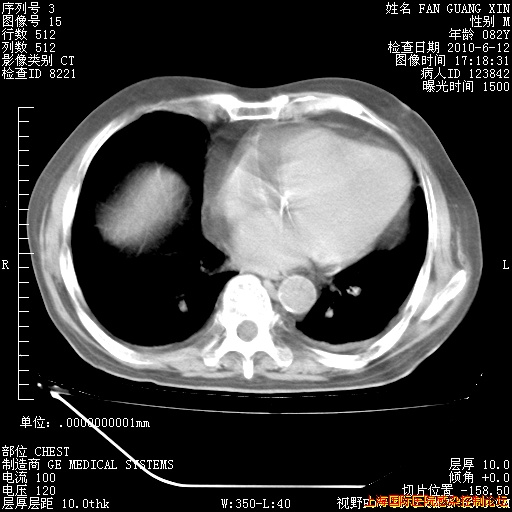

6月12日纵膈窗

整整相隔30天的肺部CT好像有所好转啊。甲强龙减量第3天,需要观察体温。

海管,自昨日你和我通完话后,不知您岳父消化道症状有无缓解?体温怎样?阅读7.12日胸部ct,个人认为目前激素治疗是有效的,甲强龙减量是适宜的。因在抗痨治疗,需密切观察肝功、肾功能和血常规。不过,老年、长期住院和大量使用激素,很担心菌群失调发生